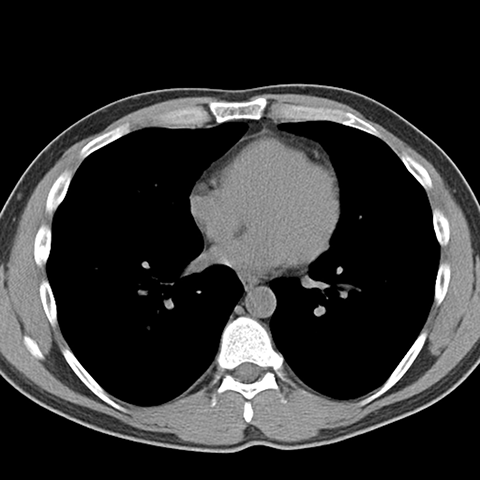

Normal Unenhanced CT (Mediastinal Window) [7 of 8]